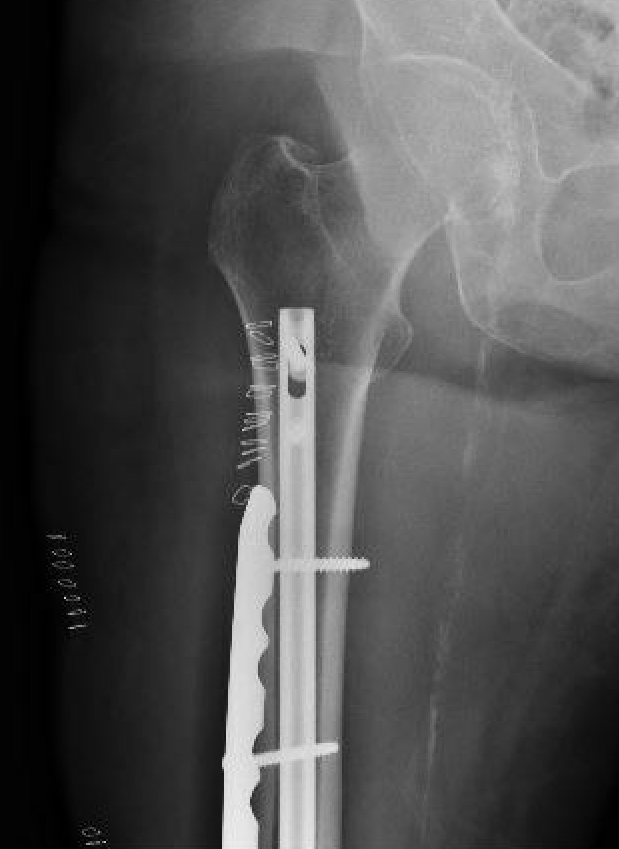

Retrograde Nail

Surgical Technique

Pass guide wire

- consider blocking screws to aid reduction

- can use femoral distractor

Blocking screws

Femoral distractor and retrograde nail

Locking screws

- distal locking performed with jig

- proximal AP locking under xray control